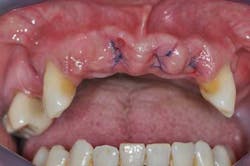

Figs. 3a, b, and c: Extraction of the upper incisors and maxillary removable acrylic placement

- Provisional acrylic removable partial denture placement after the extractions of the upper teeth. It serves as a functional and esthetic test for the rest of the treatment.